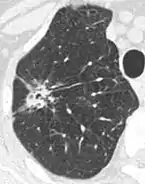

Lobulated nodule.[9]